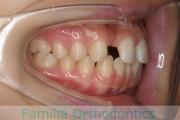

No.21V-642

- 主な症状:

- 反対咬合

- その他の症状:

- 叢生

- 年齢:

- 38歳

- 性別:

- 女性

- 抜歯部位

- 上:

- 55

- 下:

- 85|E8

- 主な使用装置:

- FEA

- 治療にかかった費用:

- 92万円

前歯の重なりと受け口を治したいということで来院されました。左下の第二小臼歯が生まれつき欠損しており、まだ子供の臼歯が残っていました。

この左下乳歯と、右下&左右上の第二小臼歯も抜歯してマルチブラケット法を行いました。

約2.5年、30回強の通院が必要でした。

反対咬合(受け口)は、前歯が咬み合わないため、奥歯に負担をかけて寿命を短くしやすいというリスクがあります。

- ≫治療前

- ≫治療後

受け口が解消するとともに、左下の永久歯欠損部分自分の歯で埋めることができましたので、今後の憂いが減ったと思います。